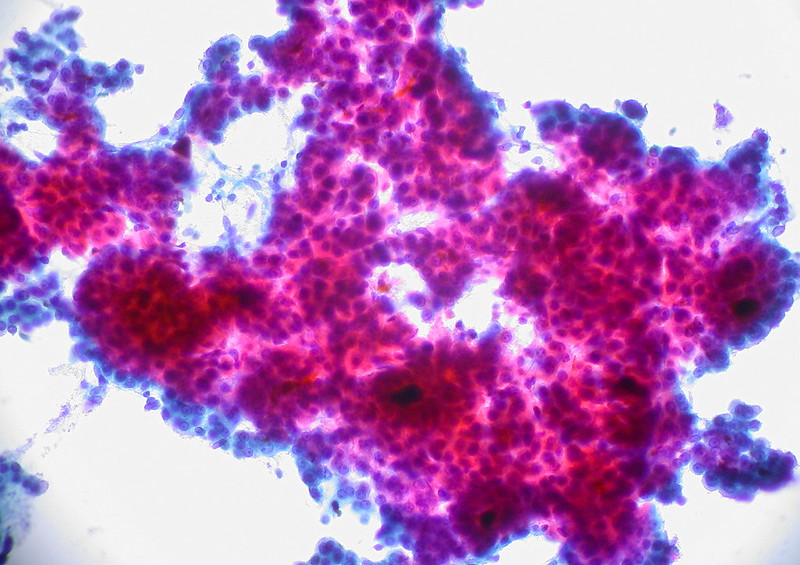

Hepatocellular Carcinoma (HCC)

Hepatocellular carcinoma (HCC) is the malignant tumor of hepatocytes, in contrast to hepatic adenoma.

Hepatocellular carcinoma (HCC) presents with severe hepatomegaly and ascites.

The prognosis of hepatocellular carcinoma (HCC) is poor.

Hepatocellular carcinoma (HCC) produces the serum tumor marker alpha-fetoprotein (AFP).

Liver Metastasis

Compared to primary liver tumors, liver metastasis is more common.

Clinical diagnosis of liver metastasis may reveal a nodular free edge of the liver and hepatomegaly.